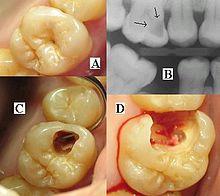

Destruction of a tooth by dental caries and disease. | |

A person experiencing caries may not be aware of the disease.[12] The earliest sign of a new carious lesion is the appearance of a chalky white spot on the surface of the tooth, indicating an area of demineralization of enamel. This is referred to as a white spot lesion, an incipient carious lesion or a "microcavity".[13] As the lesion continues to demineralize, it can turn brown but will eventually turn into a cavitation ("cavity"). Before the cavity forms, the process is reversible, but once a cavity forms, the lost tooth structure cannot be regenerated. A lesion that appears dark brown and shiny suggests dental caries were once present but the demineralization process has stopped, leaving a stain. Active decay is lighter in color and dull in appearance.[14]

As the enamel and dentin are destroyed, the cavity becomes more noticeable. The affected areas of the tooth change color and become soft to the touch. Once the decay passes through enamel, the dentinal tubules, which have passages to the nerve of the tooth, become exposed, resulting in pain that can be transient, temporarily worsening with exposure to heat, cold, or sweet foods and drinks.[15] A tooth weakened by extensive internal decay can sometimes suddenly fracture under normal chewing forces. When the decay has progressed enough to allow the bacteria to overwhelm the pulp tissue in the center of the tooth, a toothache can result and the pain will become more constant. Death of the pulp tissue and infection are common consequences. The tooth will no longer be sensitive to hot or cold, but can be very tender to pressure.

The presentation of caries is highly variable. However, the risk factors and stages of development are similar. Initially, it may appear as a small chalky area (smooth surface caries), which may eventually develop into a large cavitation. Sometimes caries may be directly visible. However other methods of detection such as X-rays are used for less visible areas of teeth and to judge the extent of destruction. Lasers for detecting caries allow detection without ionizing radiation and are now used for detection of interproximal decay (between the teeth).

Primary diagnosis involves inspection of all visible tooth surfaces using a good light source, dental mirror and explorer. Dental radiographs (X-rays) may show dental caries before it is otherwise visible, in particular caries between the teeth. Large areas of dental caries are often apparent to the naked eye, but smaller lesions can be difficult to identify. Visual and tactile inspection along with radiographs are employed frequently among dentists, in particular to diagnose pit and fissure caries.[88] Early, uncavitated caries is often diagnosed by blowing air across the suspect surface, which removes moisture and changes the optical properties of the unmineralized enamel.